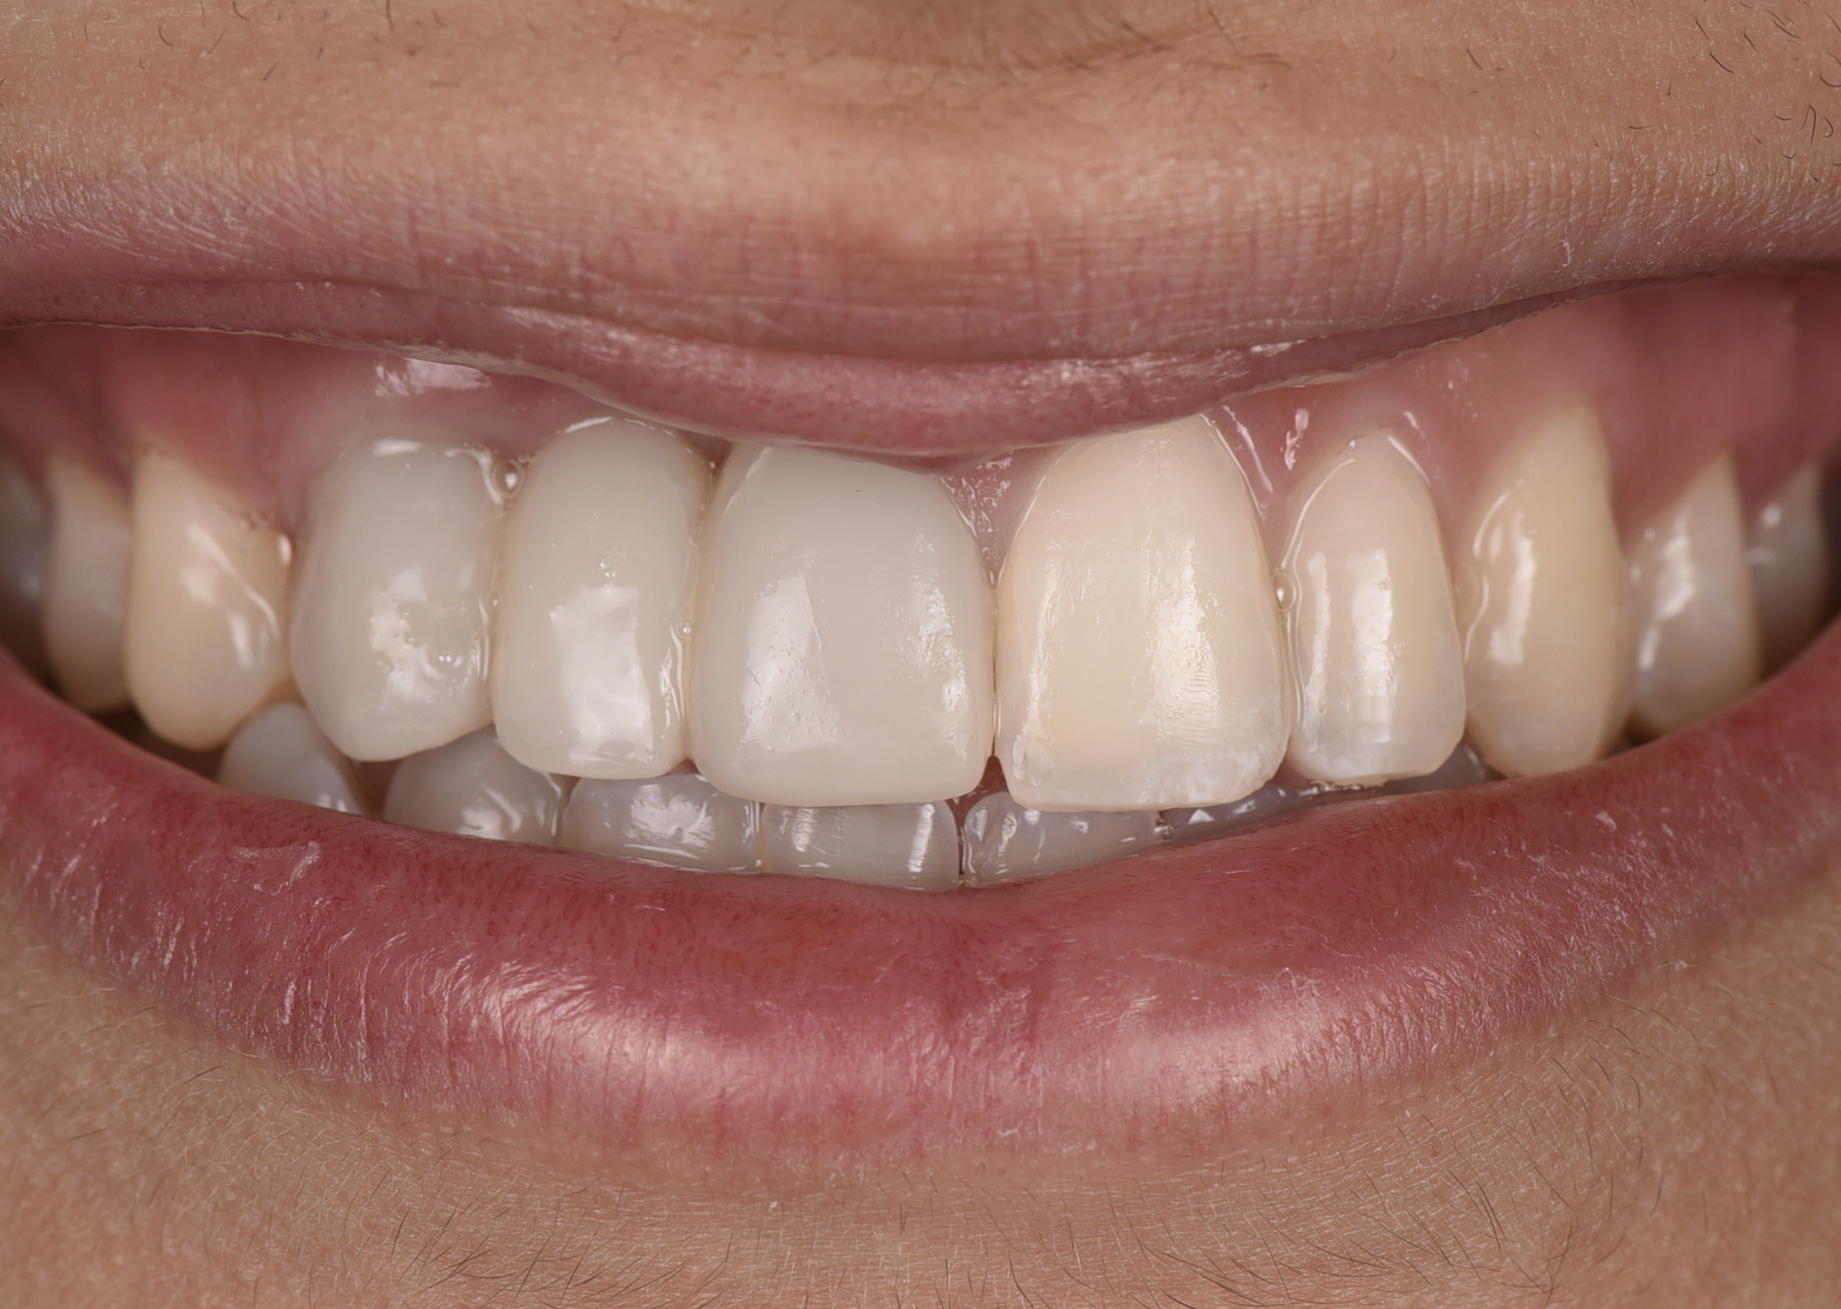

At the patient’s return visit 3 months after implant placement, the composite overlays were removed and the incisal edges of the provisional restoration were modified to approximate the length of the contralateral teeth. The patient reported no complaints, discomfort, or symptomatology throughout the osseointegration period. The implants were stable, and all discernable clinical parameters were within normal limits. The radiographic assessment revealed adequate bone-to-implant contact and osseous crest levels. Similarly, the peri-implant soft tissues displayed a healthy appearance and satisfactory gingival margin architecture (Figure 24 through Figure 27).

Fig 25. Three months post-treatment, peri-implant soft tissues appeared healthy.

Figure 25

Fig 26 . Three months post-treatment, favorable gingival architecture was preserved.

Figure 26

Fig 27. Three months post-treatment, favorable gingival architecture was preserved.

Figure 27